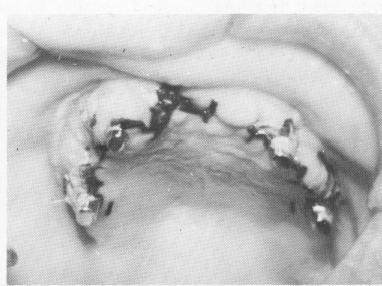

Fig. 12-81. The patient's old denture is sometimes used temporarily by first hollowing it out so it will not interfere with the four protruding posts and then relining with one of the soft reline materials, such as Hydro-Cast (Kay-See Dental Manufacturing Company) and Softtone (Bosworth Company).

The old denture in the area of the posts is hollowed out so that there is no interference (Fig. 12-81), and the denture is relined with the soft tissue conditioner. If the patient has no old denture, a new temporary denture is fabricated from the surgical bite and positioned directly over the implant framework. Postoperative instructions are once again given to the patient.

2 Old denture hollowed out & relined with Hydro Cast for temporary use